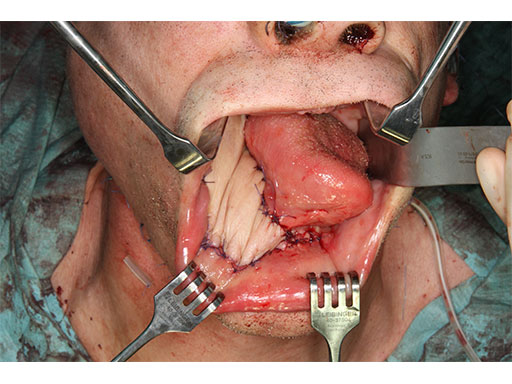

A 58-year-old male patient had oral cancer (T4n0m0) infiltrating the alveolar process and the anterior border of the ascending ramus (Fig 2). The treatment plan involved resection, bilateral neck dissection (levels I to III), and primary mandibular reconstruction with a right osteomyofasciocutaneous fibula flap.

The bony surface of the mandible is covered with a tumor infiltrated soft envelope. The SLS resection guides are screw-fixated in place.

Prior to the resection with a reciprocating saw, the plate screw holes are predrilled using a metal drill guide, which is introduced into the cylinders of the SLS resection guides.

Fig 18 Osteomyofasciocutaneous fibula flap on a side table.